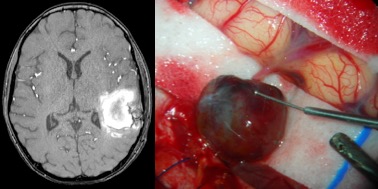

nouveau-né, infection à staphylocoque doré ; hémorragie cérébrale révélatrice d’un anévrisme mycotique - anévrysmes traumatiques : en général en regard du point d’impact